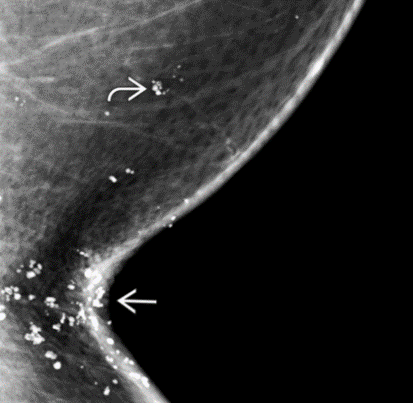

Dermatomyositis

autologous fat injection

deep oil cysts bilaterally - a lot of them

what bir-rads?

BR-2. multiple popcorn (dystrophic) calcs = multiple degenerating fibroadenomas